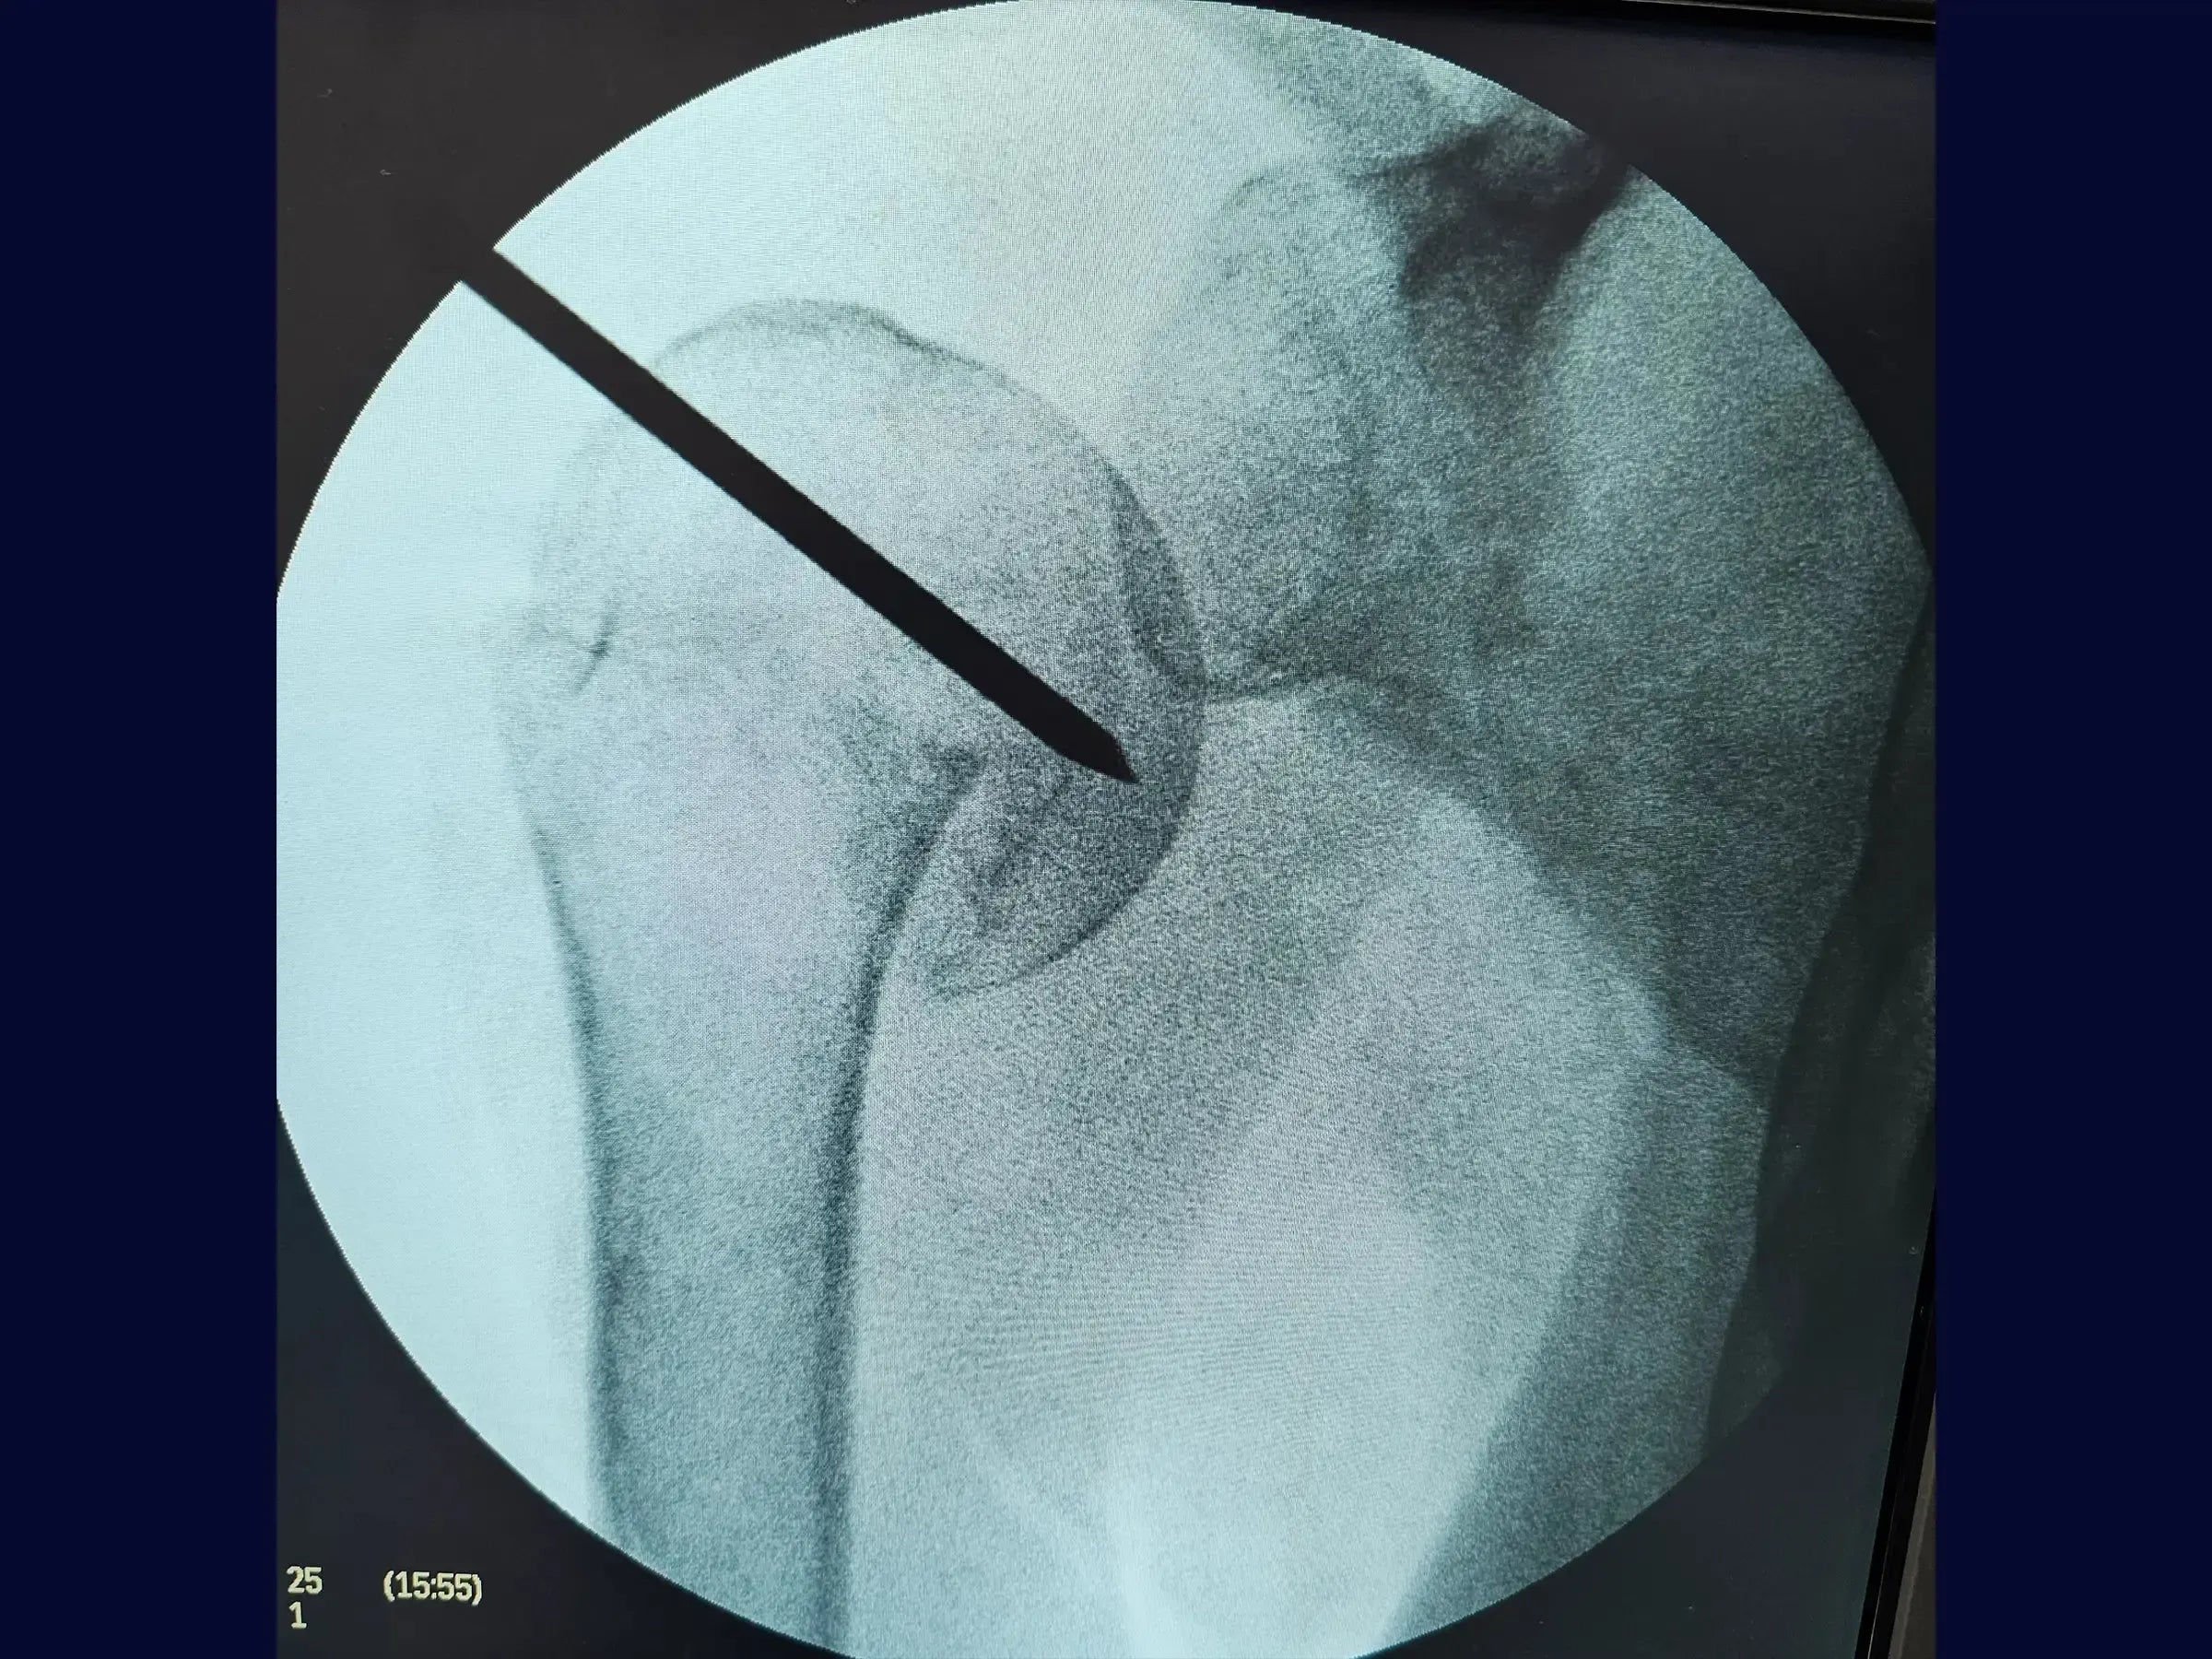

- Manipulação de fragmentos com "joystick" para otimização do ângulo de ataque.

- Manipulação do Fragmento Proximal com "Joystick": Metodologia para otimização do ângulo de ataque do fio guia, garantindo o posicionamento ideal e a melhoria da exposição da transição entre a grande tuberosidade e a cabeça umeral.

- Otimização da Introdução do Fio Guia: Estratégias para posicionamento preciso do fio guia na cabeça umeral, auxiliado por conferência radiográfica e pelo uso do "joystick" para obter imagens AP e lateral.